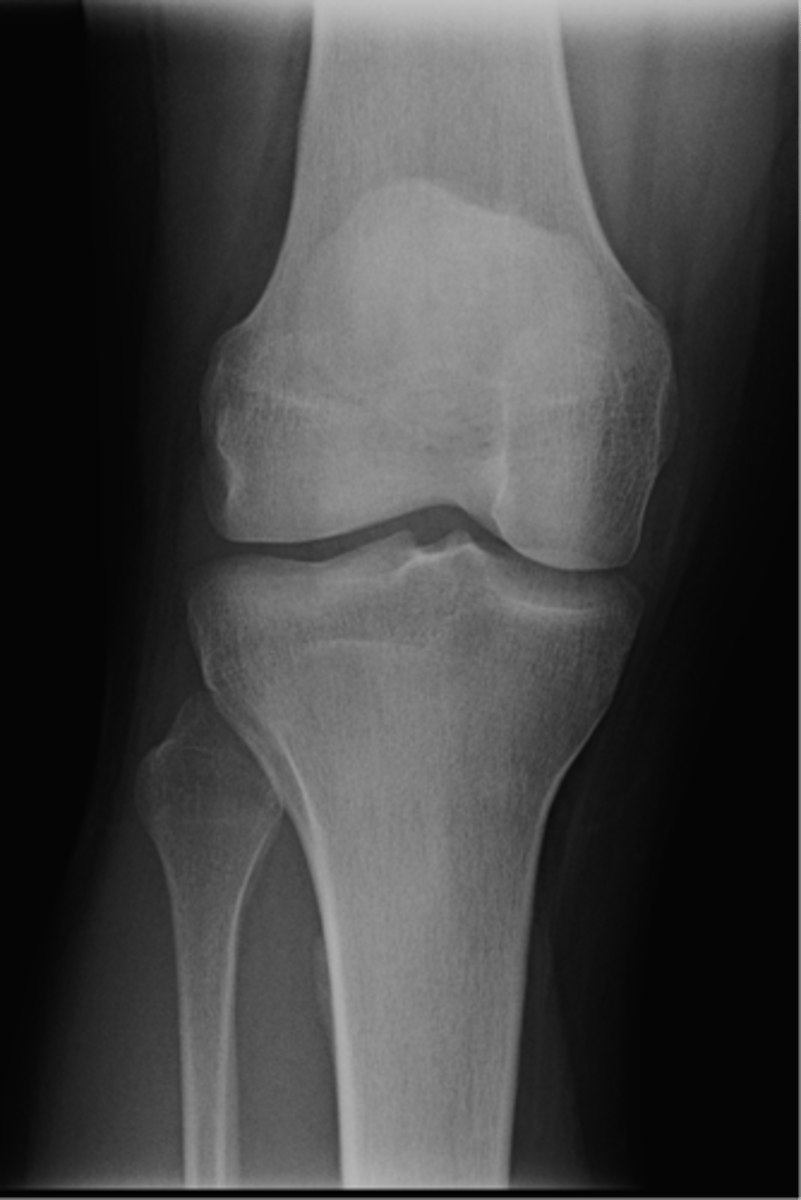

AP knee

View?

<p>View?</p>

49

New cards

Fibular head

ID 1

<p>ID 1</p>

50

Apex of fibular head

ID 2

<p>ID 2</p>

51

Fossa for popliteal tendon

ID 3

<p>ID 3</p>

52

Intercondylar eminence

ID 4

<p>ID 4</p>

53

Superior aspect of patella

ID 5

<p>ID 5</p>

54

Lateral femoral condyle

ID 6

<p>ID 6</p>

55

Medial femoral condyle

ID 7

<p>ID 7</p>

56

Intercondylar fossa

ID 8

<p>ID 8</p>

57

Apex of patella

ID 9

<p>ID 9</p>

58

Lateral femoral epicondyle

ID 10

<p>ID 10</p>

59

Medial femoral epicondyle

ID 11

<p>ID 11</p>

60

Tibial tuberosity

ID 12

<p>ID 12</p>

61

Medial tibial plateau

ID 13

<p>ID 13</p>

62

Lateral tibial plateau

ID 14

<p>ID 14</p>

63

Medial tibial condyle

ID 15

<p>ID 15</p>

64

Lateral tibial condyle

ID 16

<p>ID 16</p>

65

Physeal scar

ID 17

<p>ID 17</p>

66

Adductor tubercle

ID 18

<p>ID 18</p>